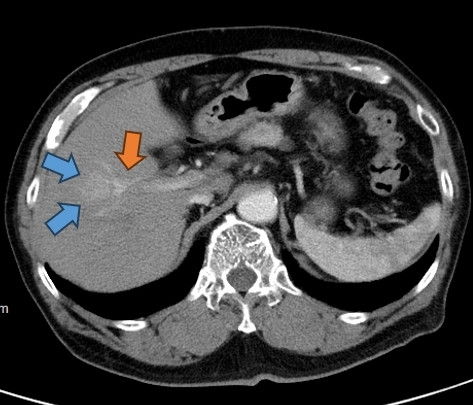

〔記者王俊忠/台南報導〕67歲陳先生是B型肝炎帶原者,長期在診所追蹤,後來超音波發現肝臟右側出現1顆3公分大的腫瘤,轉診成大醫院進一步做腹部電腦斷層,研判腫瘤極可能是原發性肝癌,因腫瘤貼近右前葉肝臟的肝門靜脈、尚未有肝硬化表徵,在期望完全根治的考量下,患者決定接受手術評估。

成大醫院外科部主治醫師楊宗翰指,陳先生抽血檢查顯示肝功能無明顯異常,但胎兒蛋白指數升高。醫療團隊進一步以3D立體影像重組,模擬切除右前葉肝臟,仍可保留約60%肝臟,具備安全手術條件。手術過程運用靛氰綠(ICG)螢光染色技術,清晰辨識右前葉肝臟血管供應範圍,以微創手術精準切除肝病灶範圍,手術出血量在100ml以內。陳先生術後恢復良好,第5天出院,後續每3-6個月門診追蹤,迄今滿2年未見復發跡象。